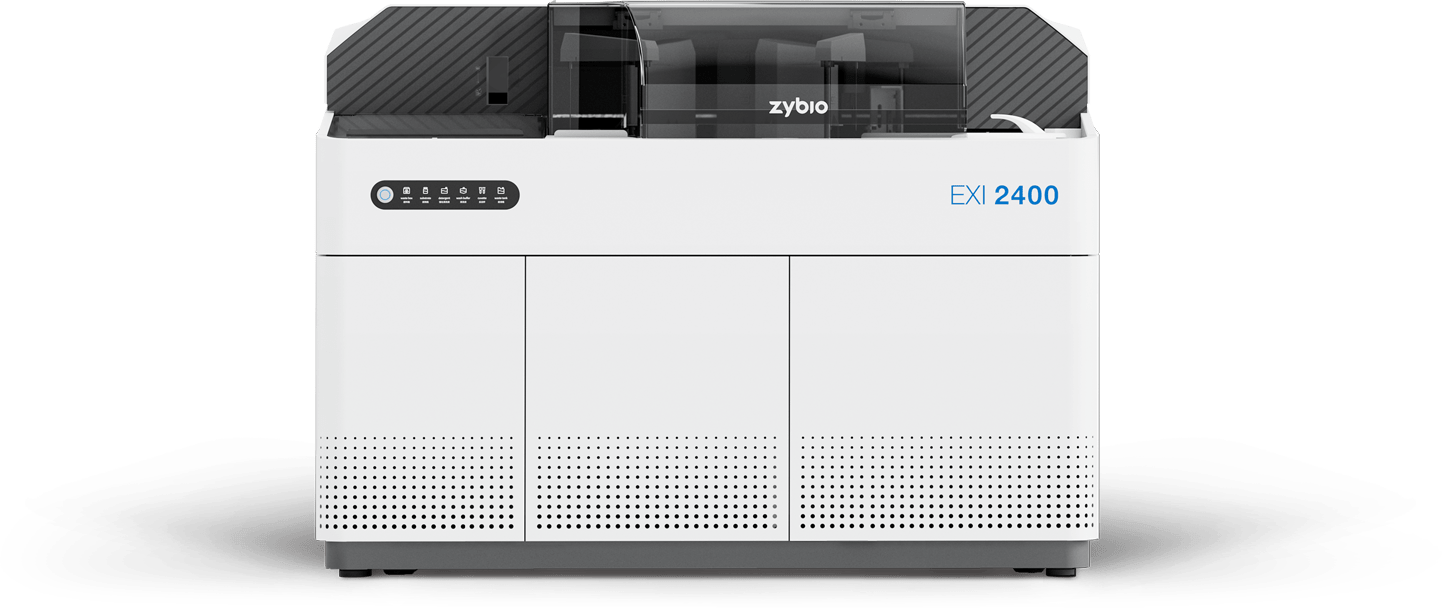

EXI 2400

全自动化学发光免疫分析仪

400 T/H

单机检测速度

13 min

首结果时间

28 个

试剂位

100 个

样本位

1200 个

反应杯一次存储量